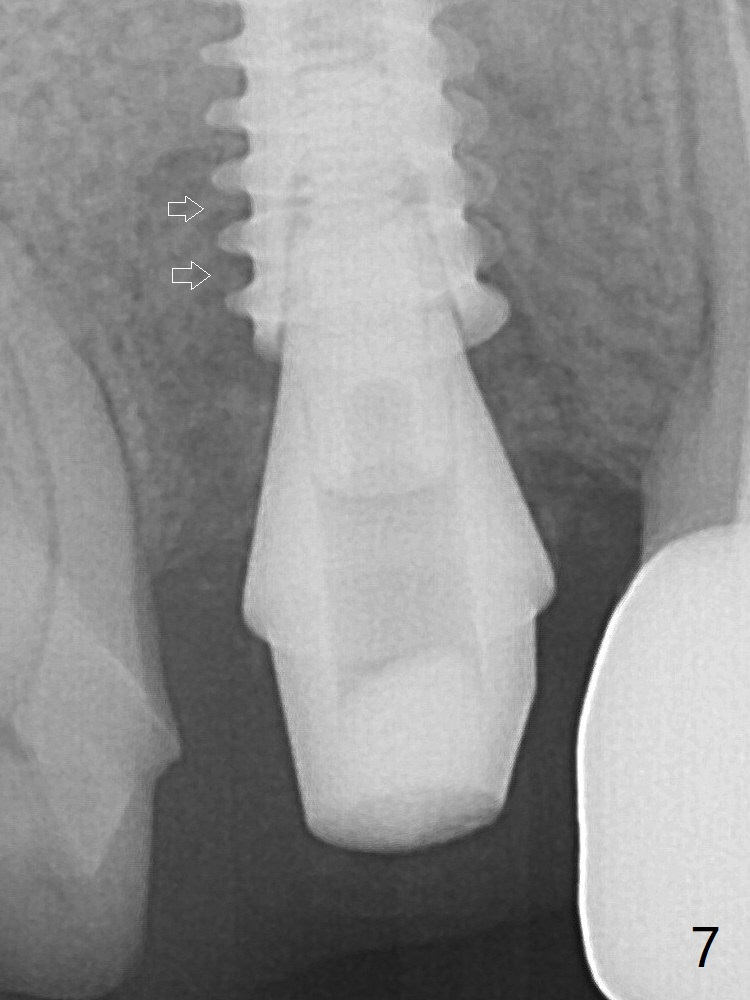

To reduce the gap and periimplantitis, a 5x11 mm IBS implant is placed with insertion torque > 50 Ncm after further osteotomy using Magic Drills (Fig.4). Following placement of 5.5x4(4) mm abutment (A), a splinted provisional is fabricated at #3 and 4. The provisional is stable 3 months postop (Fig.7). Bone graft appears to remain between the implant fins (arrows). The bone density of the bone graft between the implant fins increases 4.5 months postop (Fig.9).